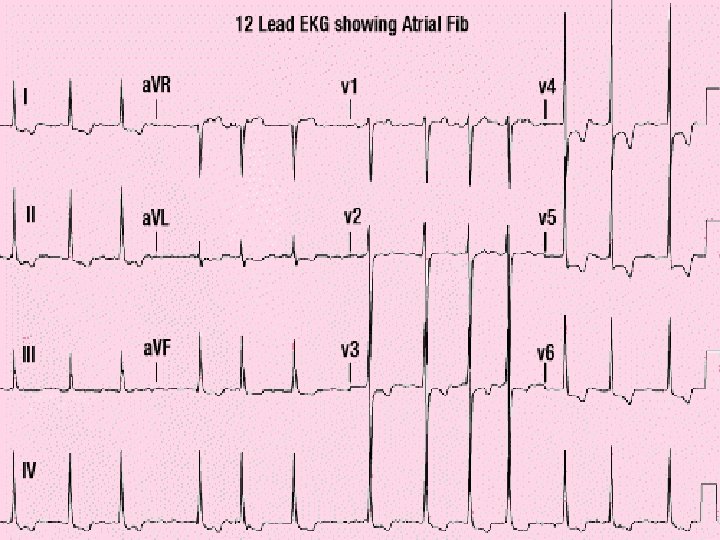

Conduction • Occurs approximately every 0. 8 seconds. • Electrical impulse can be recorded on an EKG • Used to detect abnormal activity or disease.